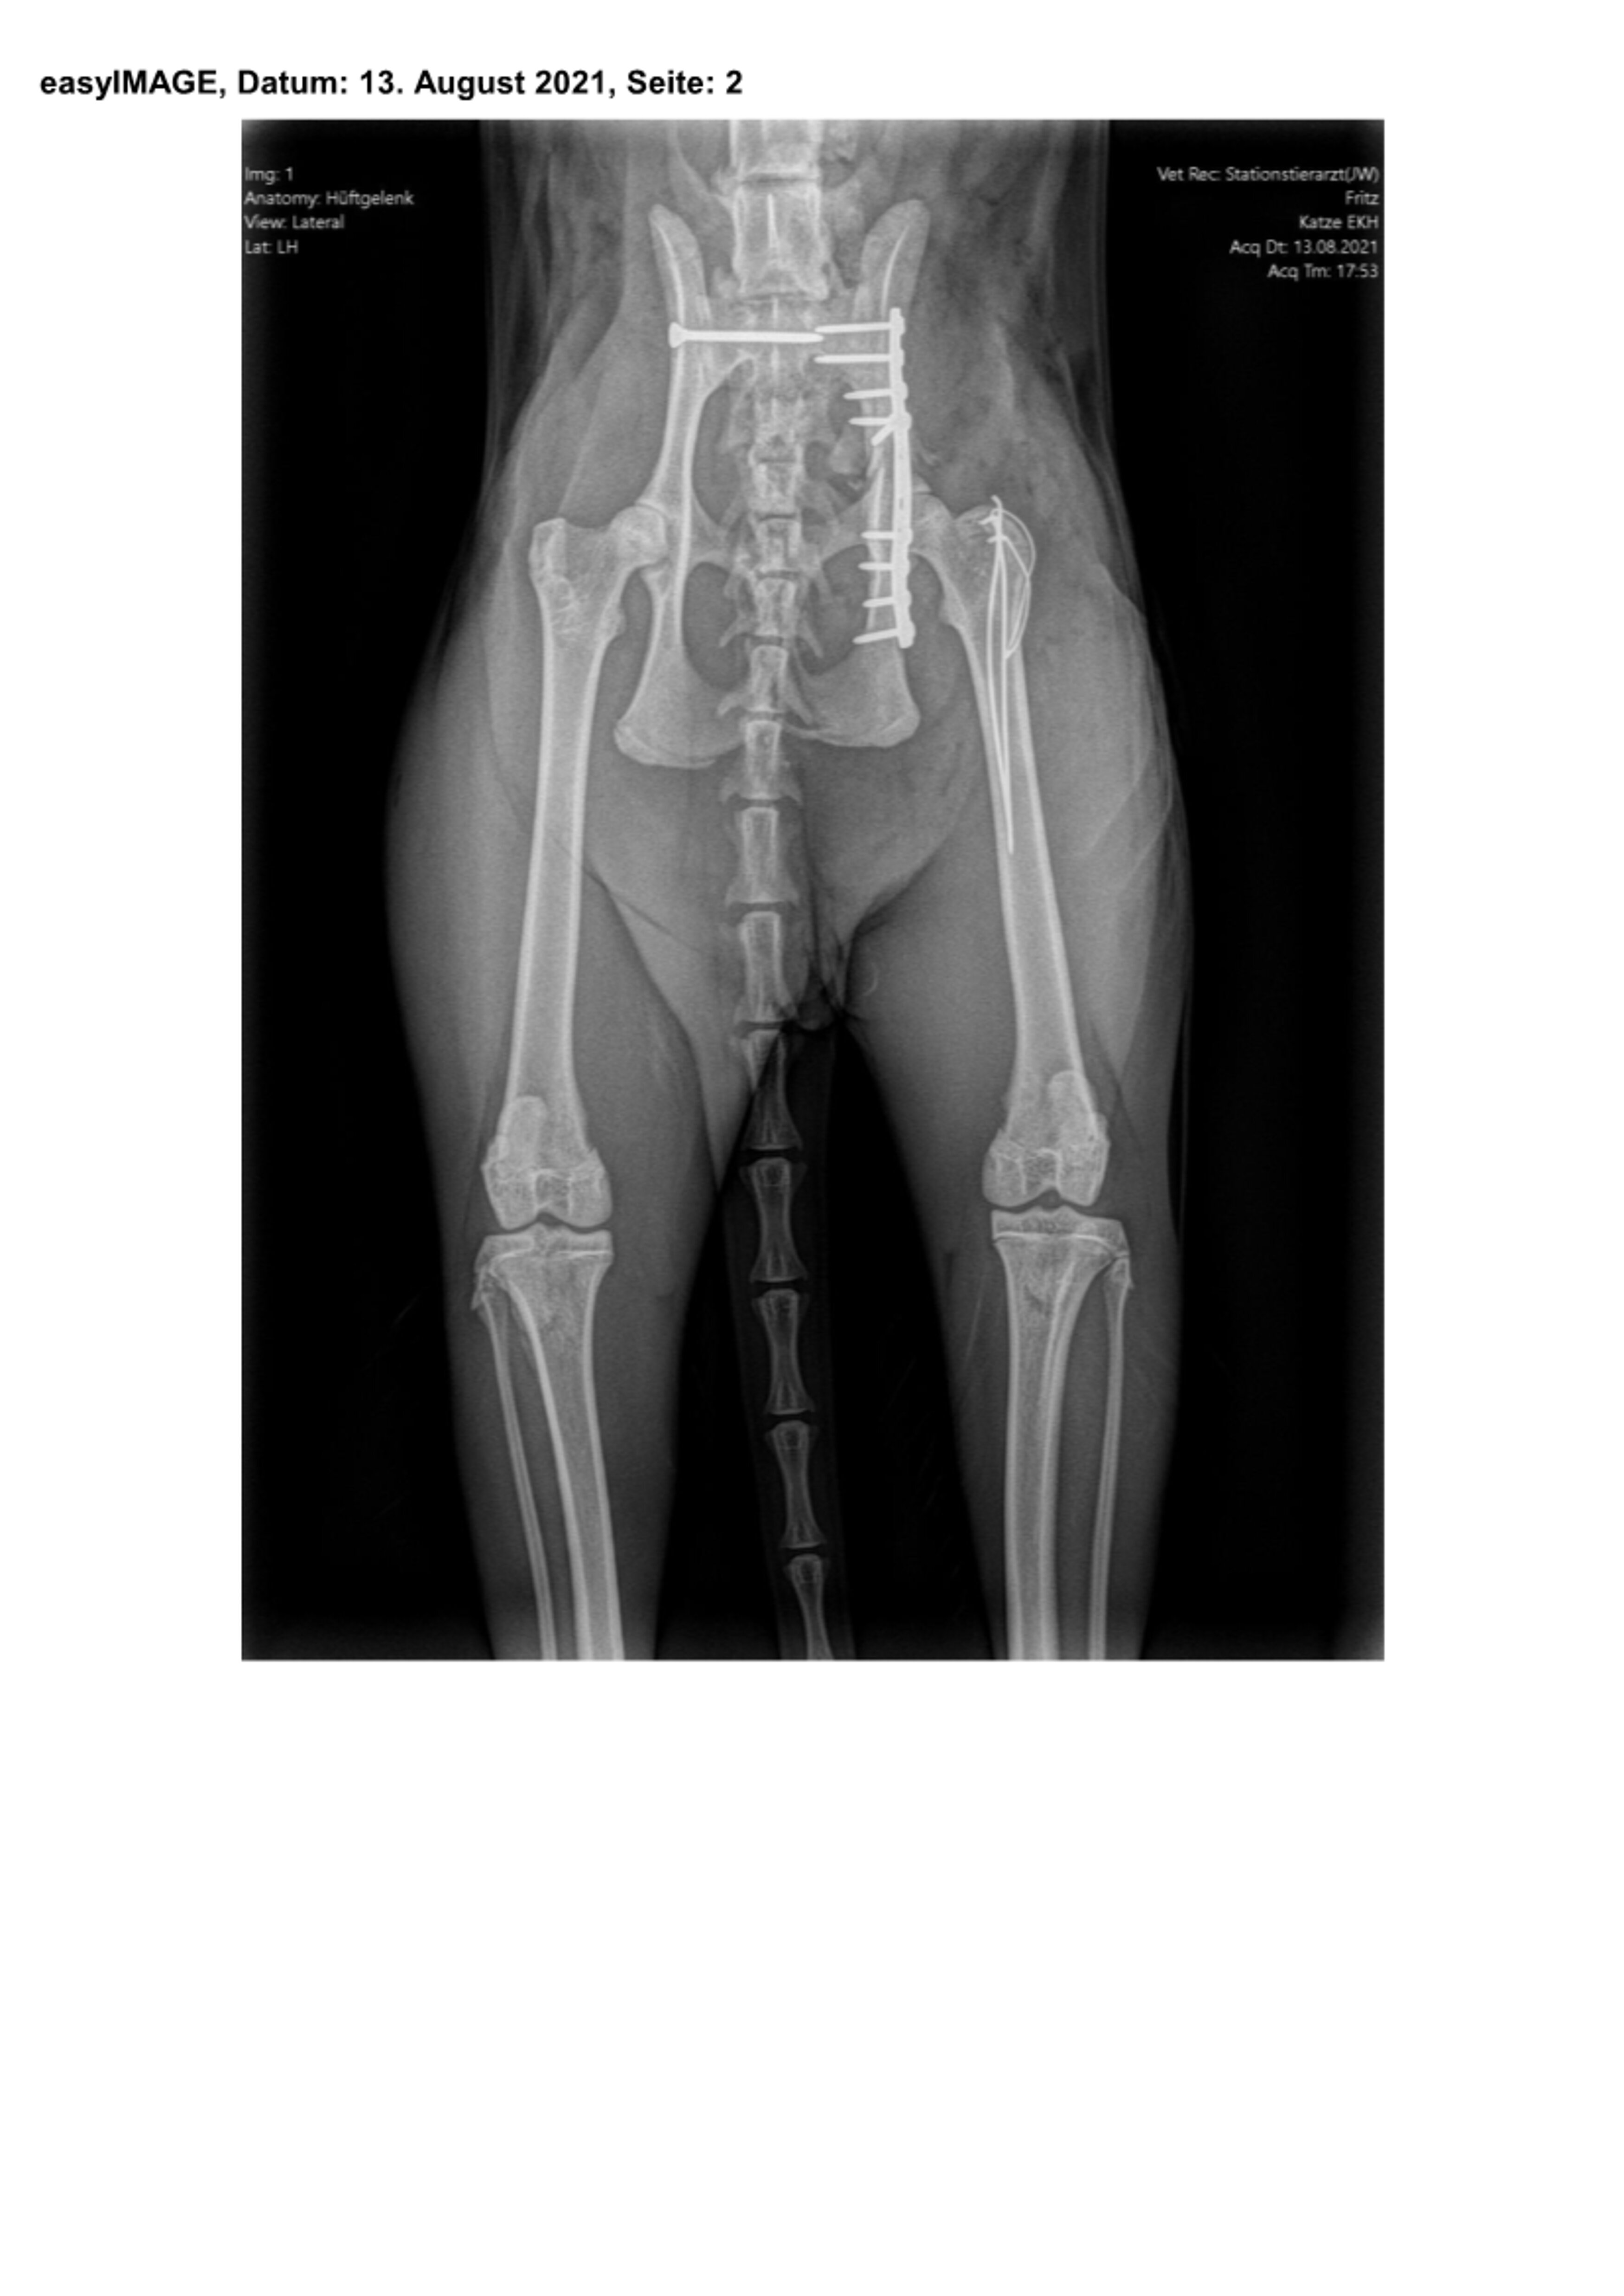

Am 13. August, also fünf Tage nach dem Unfall, entschied man sich dann zur Operation, da die Verlaufsuntersuchung dank der wiedergewonnenen Reaktionsfähigkeit des Patienten jetzt den Verdacht einer begleitenden Verletzung des rechten Ischias Nerven aufkommen ließ. Durch Vorbiegen einer Knochenplatte an einem Beckenmodell wurde der Eingriff sorgfältig vorbereitet, um die Operationszeit möglichst kurz halten zu können.

Zuerst wurden das ausgerenkte rechte Kreuz-Darmbein-Gelenk sowie der in seiner unmittelbaren Nachbarschaft verlaufende Ischias dargestellt und das Darmbein nach seiner Reposition mit einer 2,0 mm dicken und 24 mm langen Schraube an den Kreuzbeinkörper fixiert. Nach dem Wundverschluss wurde der Kater auf die andere Körperseite gelagert und sodann der direkt vor der Hüftgelenkspfanne Eine weitere Schraube diente der Adaptation eines Darmbeinsplitters an die Hauptfragmente. Da die Freilegung dieser Beckenregion meistens auch einen Knochenschnitt am Oberschenkel zum Verlagern der Kruppenmuskeln erfordert, wurden die Endsehnen dieser Muskeln mit dem knöchernen Segment abschließend durch 2 Bohrdrähte und einer 8-förmigen Drahtschlinge wiederbefestigt.

Röntgenbilder mit freundlicher Genehmigung Tierklinik Weilheim.